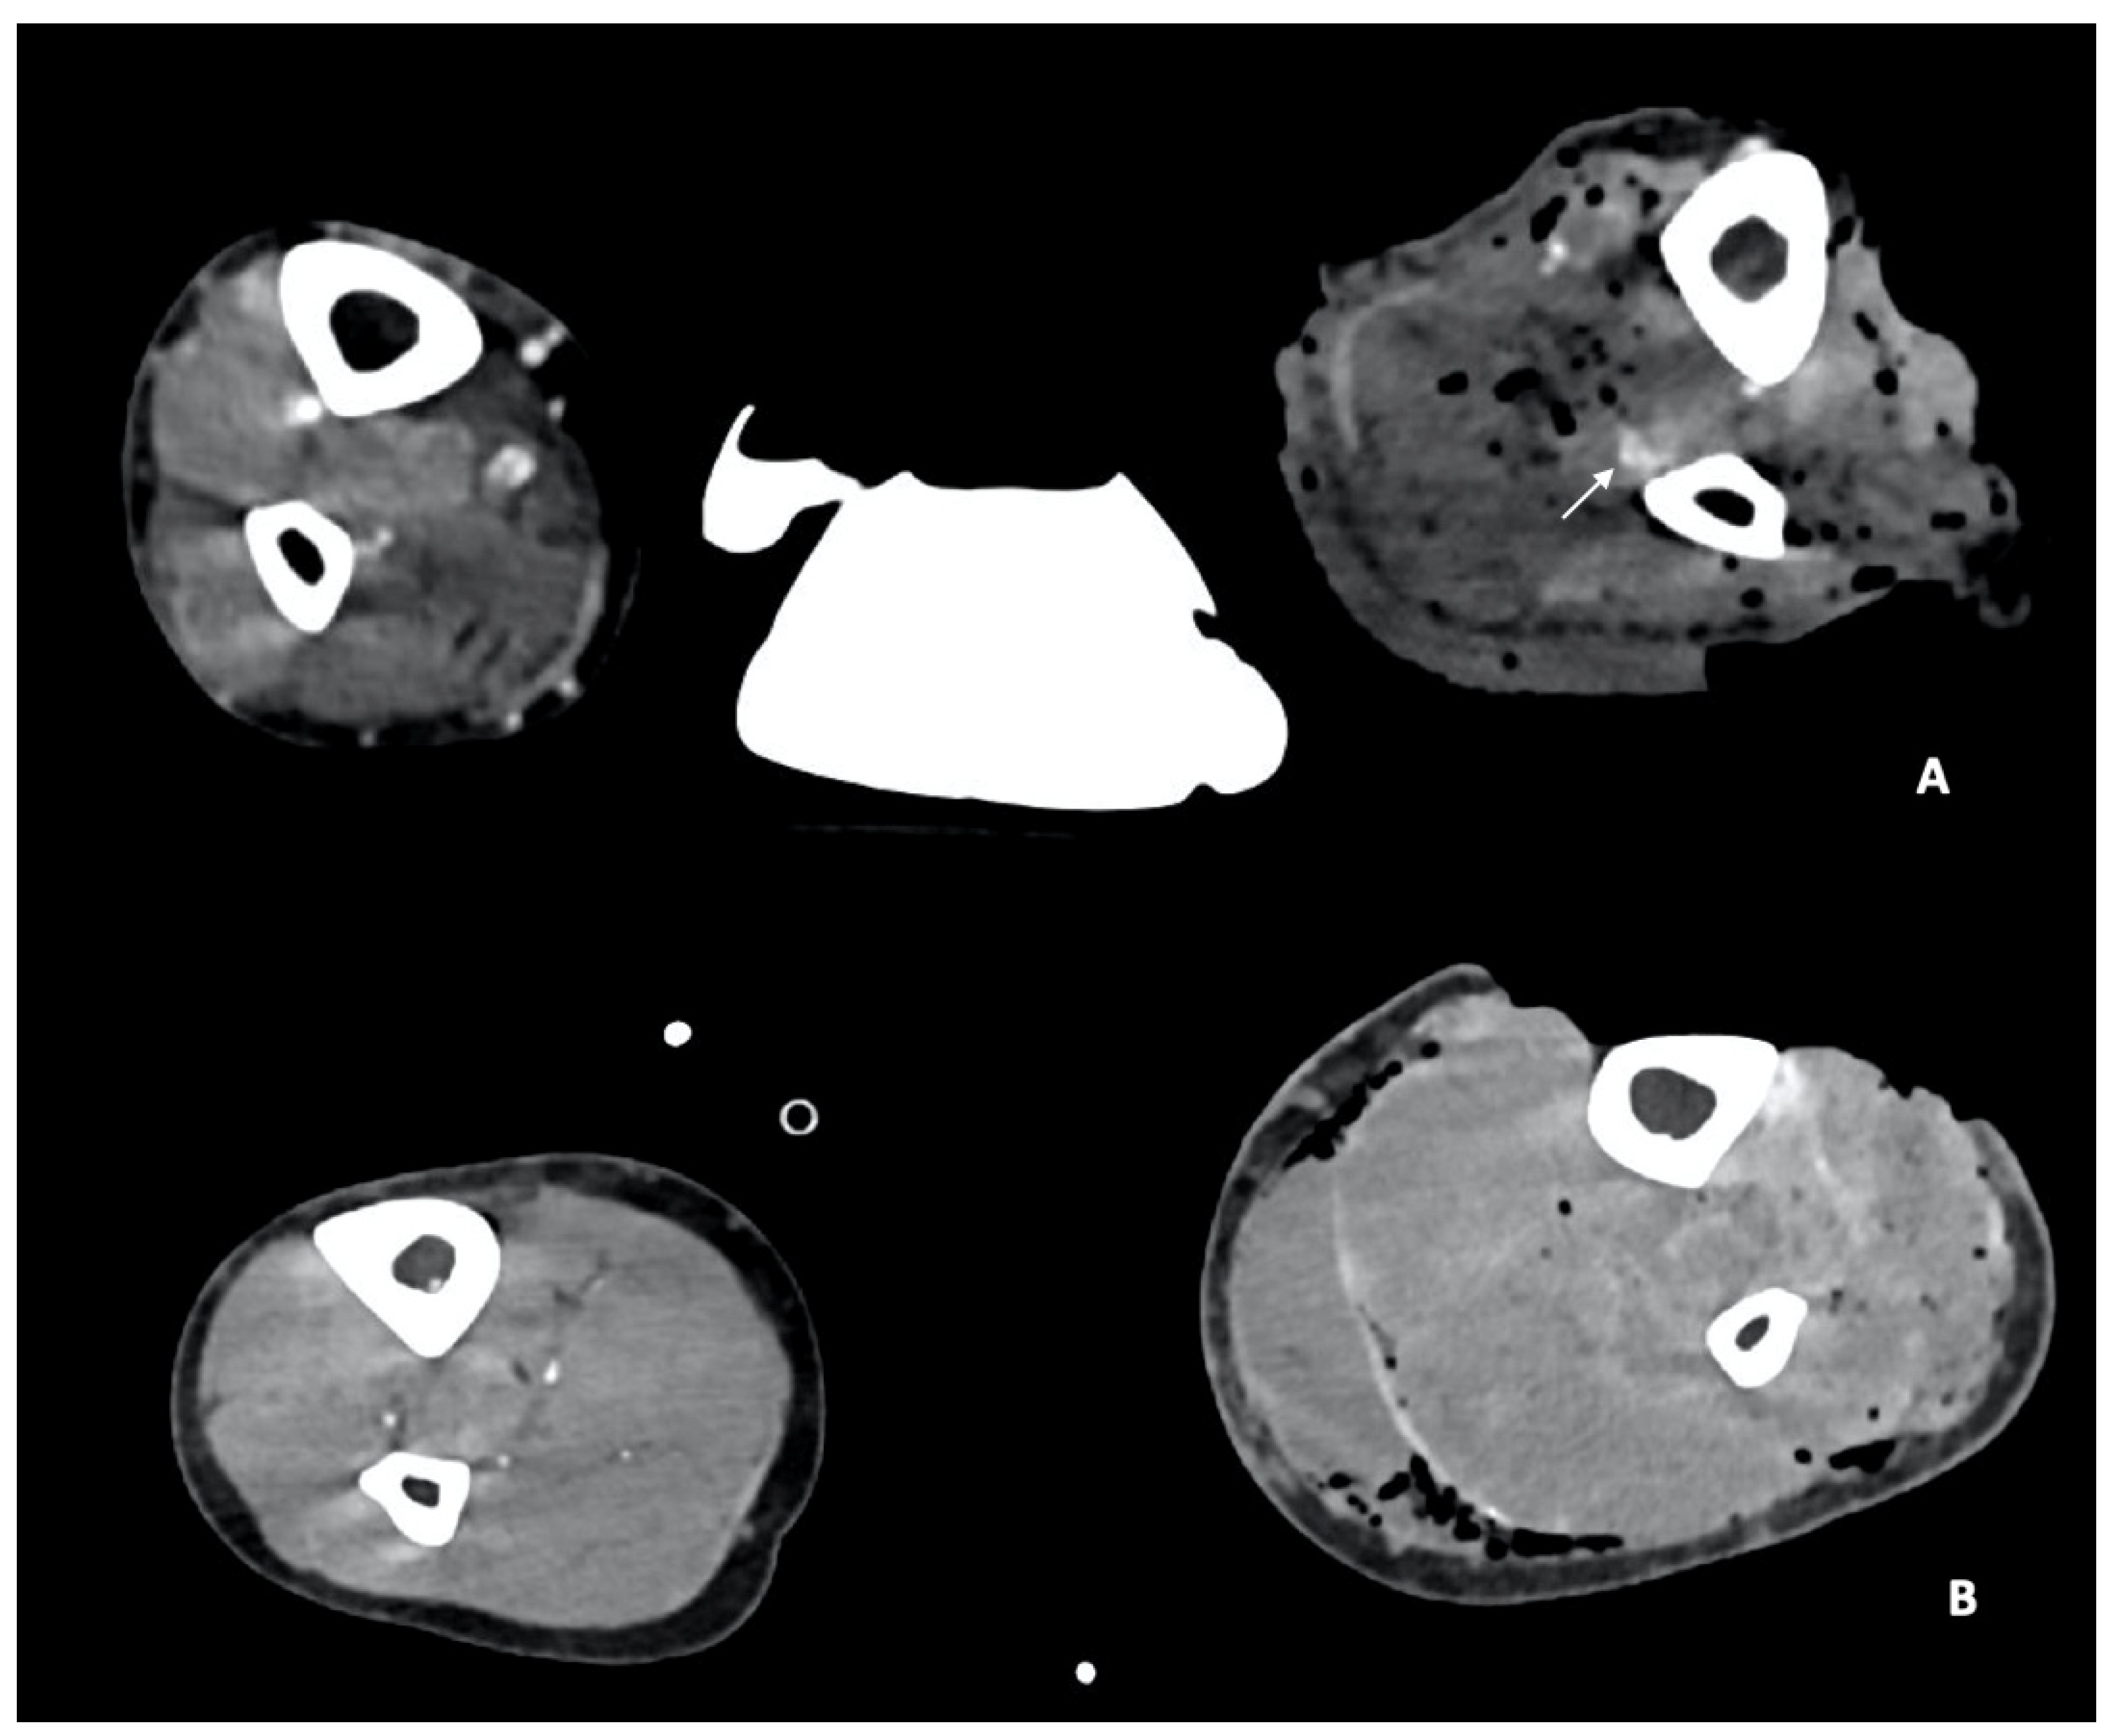

- Arterial Transections represents the complete rupture of the vessel, and determines the loss of distal opacification, a massive hematoma and active bleeding [5] (Figure 3). Active arterial bleeding is visualized as contrast extravasation in the arterial phase, which enlarges in venous and delayed phases [67]. In partial transection, the arterial tear involves the three layers of the vessel wall, without affecting the entire vessel’s circumference, distal opacification is appreciable although reduced luminal caliber and opacification can be detected [5,55].

- Luminal narrowing: the vessel wall appears lobulated with eccentric narrowing, it can be the result of extrinsic compression, non-occlusive thrombus, or dissection (Figure 3).